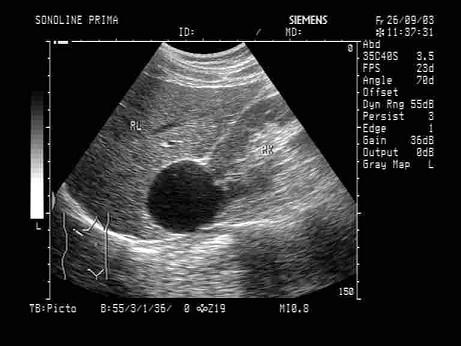

问题 根据声像图,最可能的诊断为?(?)

选项 A.肝囊肿 B.肾囊肿 C.肾上腺囊肿 D.嗜咯细胞瘤 E.肾脓肿

答案 B